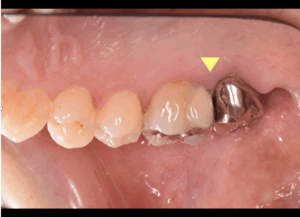

見えにくいむし歯や歯と歯の間のトラブルが関係することもあります

歯と歯の間のむし歯は見た目ではわかりにくく、汚れもたまりやすい場所です。そのため、むし歯のせいで歯ぐきに炎症を起こすこともあります。

実際には、出血の主な原因は歯肉炎や歯周病であることが多いですが、そこにみがき方や歯と歯の間のトラブルが重なっていることがあります。原因を正しく見極めるには、歯科で確認するのが安心です。

冷たいものがしみる、食べものが詰まりやすい、毎回同じ場所から出血する場合は、歯ぐきだけでなく歯そのものにも原因があるかもしれません。見えにくいむし歯や清掃しにくい部位のトラブルが隠れていることもあります。